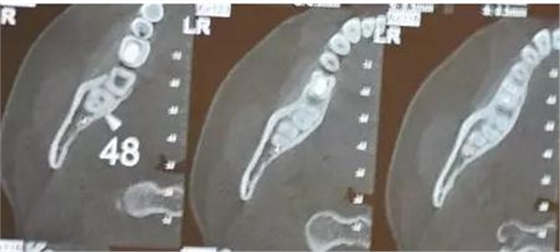

患者、女、24歲,主訴:右側(cè)下后牙自發(fā)疼數(shù)月。專科檢查:48垂直位、萌出約1/2,合面齲壞,探痛明顯,全景片檢查;48牙根與下頜管重疊,加拍CBCT檢查:下頜管位于48根尖下方的舌側(cè),牙根并未進入下頜管內(nèi)。診斷:48中位垂直阻生伴牙髓炎。治療計劃:建議拔除48.患者同意治療方案,簽術(shù)前知情同意書。

圖4.CBCT的水平斷面檢查:48牙根不在下頜管內(nèi),但與下頜管緊鄰